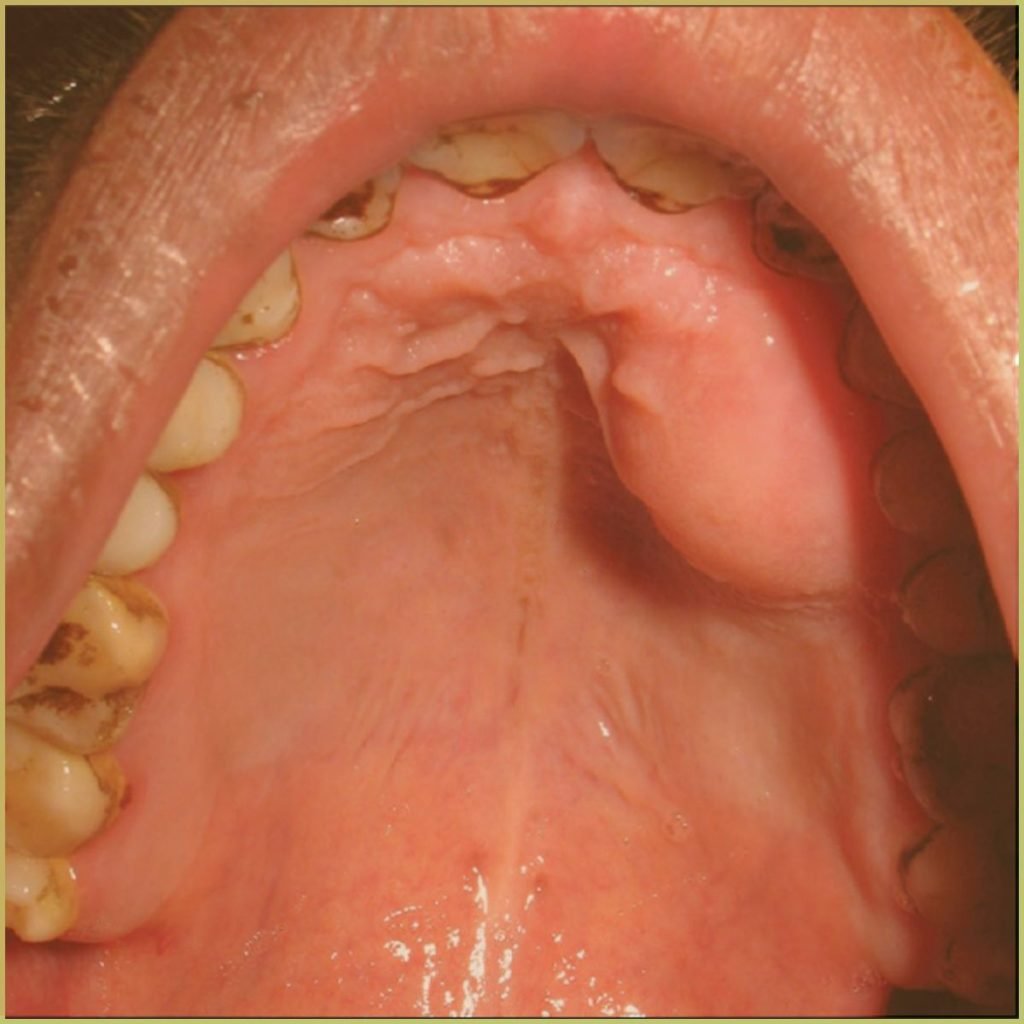

FIBROUS HYPERPLASIA

Fibrous Hyperplasia (Epulis Fissuratum) describes inflammatory hyperplasia of fibrous connective tissue in response to localized low-grade irritation or trauma. It is commonly associated with ill-fitting dentures. The common clinical presentation includes:

- Rounded folds of broadly based fibrous tissue.

- Ulceration is often noted at depth of tissue folds.

- A polypoid or leaf-like appearance may be noted on the hard palate.

- Commonly seen on vestibular mucosa at the periphery of a denture flange.

Diagnosis is based on the lesion history and clinical presentation only. Your differential diagnosis should include:

- Lymphoma.

- Soft tissue tumor (fibroma, Kaposi sarcoma, liposarcomas etc).

- Metastatic tumor.

Treatment involves lesion excision and denture reline or replacement.